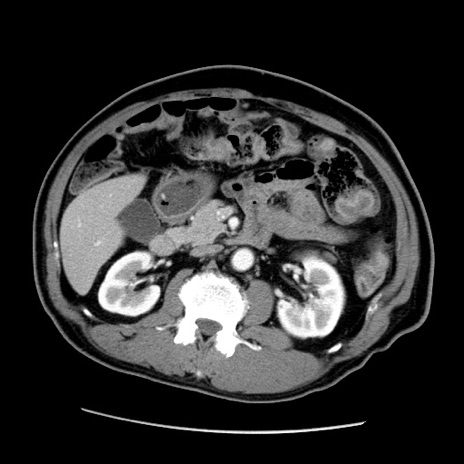

症例22(横断像)

【症例】50歳代男性

【主訴】腹痛

【現病歴】AVMからの被殻出血のため回復期リハ病棟入院中。 本日午後3時頃急に下腹部痛が出現した。

【既往歴】AVM、被殻出血、虫垂炎、高血圧

【身体所見】意識晴明、左半身不全麻痺、会話の理解は良好、36.5°C、腹部:膨隆、全体に板状硬、下腹部正中に圧痛点あり、反跳痛-、筋性防御不明、右下腹部にope scar

【データ】WBC 9400、CRP 0.06